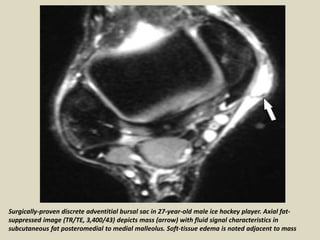

Surgically-proven discrete adventitial bursal sac in 27-year-old male ice hockey player. Axial fat-

suppressed image (TR/TE, 3,400/43) depicts mass (arrow) with fluid signal characteristics in

subcutaneous fat posteromedial to medial malleolus. Soft-tissue edema is noted adjacent to mass